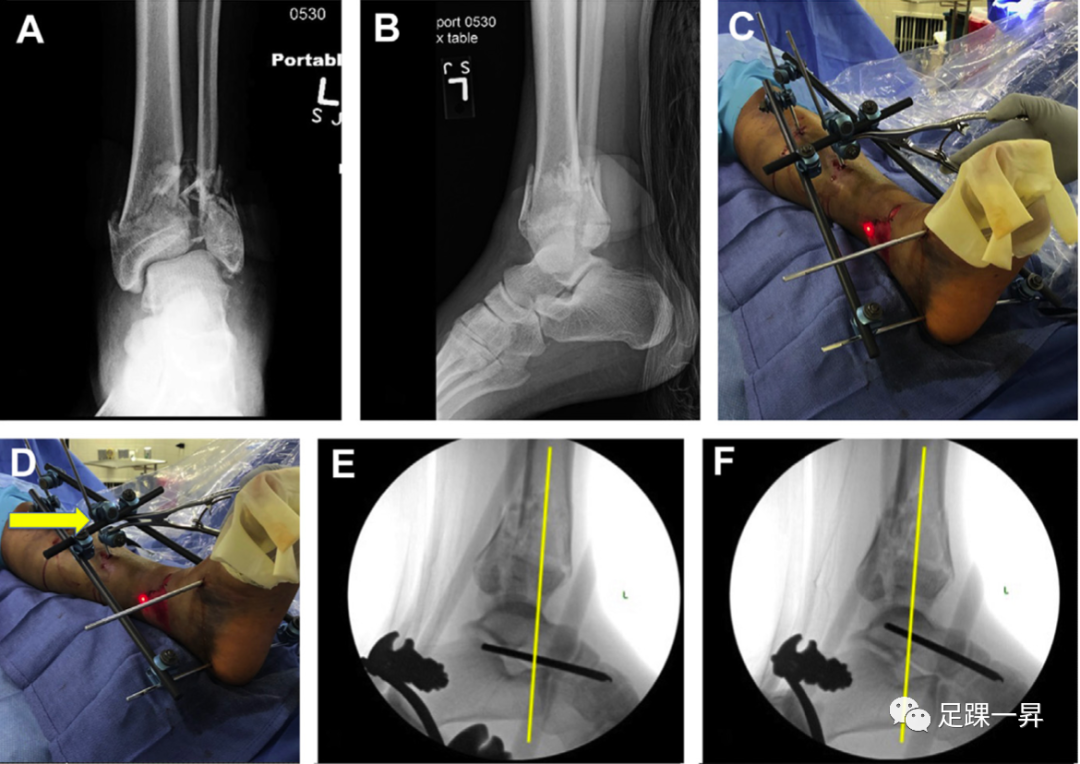

△图示一例多发伤和双侧pilon骨折患者接受了外固定治疗。

最近的研究集中在外固定策略的优化上。有限元分析显示,与Mitkovic(单轨)和单侧固定器配置相比,Delta框架在模拟步态过程中的相对微动最低。将前足保持在跖行姿态需要将Schanz针放置到中足或前足中。有趣的是,一项回顾性研究表明,在踝关节外固定中添加第一跖骨固定钉产生的复位丢失率与不使用第一跖骨钉的情况相当。然而,力线的微小变化在临床上的重要程度尚不清楚;外固定是牵引的一种形式,主要目的是保持长度和力线,并保护软组织,直到可以进行确定的手术。

△图示踝关节Delta框架外固定架。

△图示外固定中添加第一跖骨固定钉将前足保持在跖行姿态。